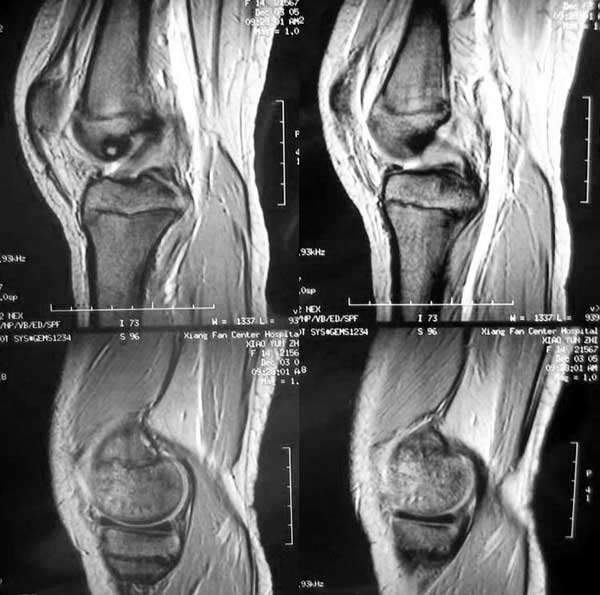

14岁女孩,7月前右膝关节疼痛,进行性加重,无外伤,无潮热盗汗,无高热,未治疗。1周前入院,下肢皮肤牵引,抗炎治疗,症状减轻。入院查右膝关节轻肿,浮膑(-),碱性磷酸酶140,余(—)。如何诊治?1周前ct 见关节面破裂,关节腔穿刺少量血性液:细胞学检查示滑膜炎改变,培养未见细菌生长。 7月前ct

6月前mri,1周前ct

考虑结核可能性大,骨样骨瘤待排;结核单关节病变好发于承重关节,髋关节、膝关节病变占80%左右,关节局部疼痛、肿胀,活动受限,起病缓慢。骨样骨瘤多发生在长骨的骨皮质,很少部分发生在骨松质,以股骨、胫骨最常见,病灶周围有显著的反应性硬化环,局部疼痛,夜间较重,近关节的病灶有关节积液。本病例应进一步做其他检查。

低毒感染,骨样骨瘤待排,mri表现整个骨够信号异常并跨够线,良性肿瘤基本排除,(但骨样骨瘤与骨母与感染有关),病灶周边硬化不是tb表现。

病变骨质增生硬化,不支持结核。mri示病变中心内短t1、长t2信号,考虑为骨样骨瘤并瘤巢内出血。

病变特点:股骨的非负重区的破坏病灶,病灶边沿的硬化明显,ct mri均显示病变为慢性过程,关节积液不明显,考虑低毒感染可能性大,请继续抗炎治疗,不除外骨样骨瘤

病变特点:病灶较小,周围硬化环厚/明显,中心ct呈透光区,mr可见液性成分;14岁小孩,骺端关节面的病变,可考虑的病变有:1/低毒力感染,嗜酸性肉呀肿,2/软骨母细胞瘤,年龄/好发部位/信号/密度均可符合诊断,唯一不支持的是病灶中心未见点状钙化或骨化影3/腱鞘囊肿4/巨细胞瘤和骨囊肿可以不考虑。

骨骺轻度水肿,近髁间凹关节面侧骨局灶性破坏,病灶边缘有较多的环形硬化,骨显著硬化是细菌性感染的特点,关节积液不明显...抗炎治疗症状减轻,考虑为低毒感染可能性大(brodie骨脓肿可能).请继续抗炎治疗